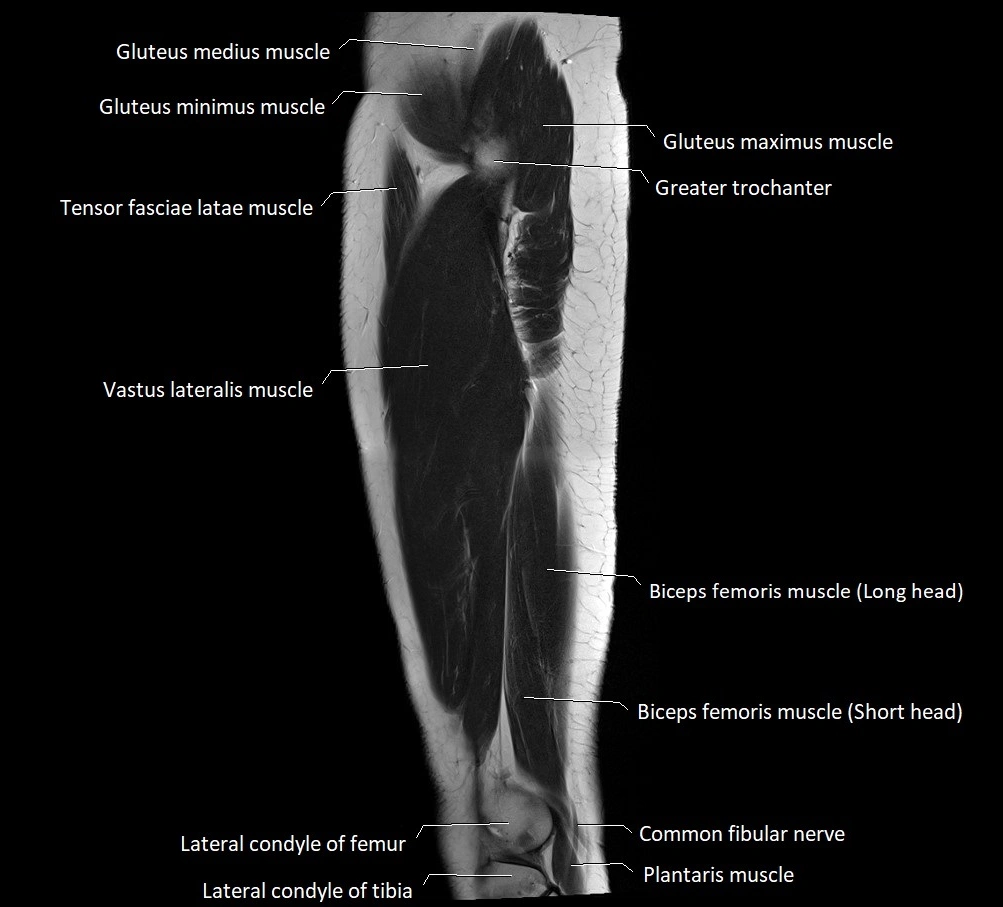

- Biceps femoris muscle (Long head)

- Biceps femoris muscle (Short head)

- Common fibular nerve

- Gluteus medius muscle

- Gluteus minimus muscle

- Greater trochanter

- Lateral condyle of femur

- Lateral condyle of tibia

- Plantaris muscle

- Tensor fasciae latae muscle

- Vastus lateralis muscle